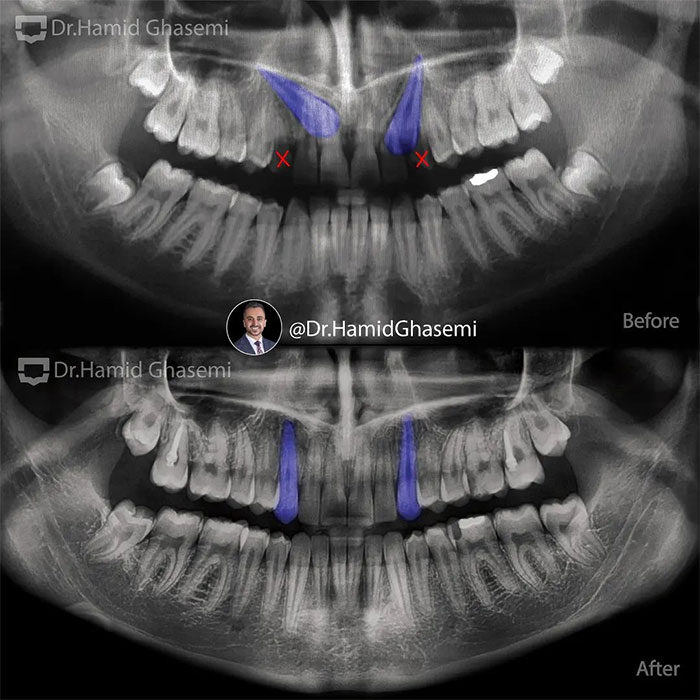

درمان ارتودنسی در کیس با مشکل نهفتگی دو طرفه دندانهای نیش فک بالا.

Orthodontic treatment of case with bilateral impacted upper canines.